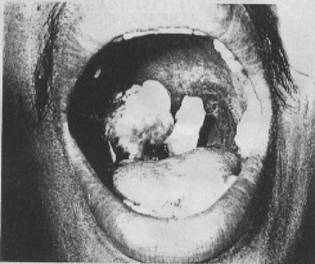

แอนแทรกซ์ในปากและคอหอย

ติดโดยการกินเช่นเดียวกับแอนแทรกซ์ที่ทางเดินอาหาร ผู้ป่วยจะแสดงอาการเจ็บคอ คอบวม แข็งตึง และกลืนอาหารลำบาก เพราะมีแผลเนื้อตายที่คอและคอหอย (รูปที่ 7)